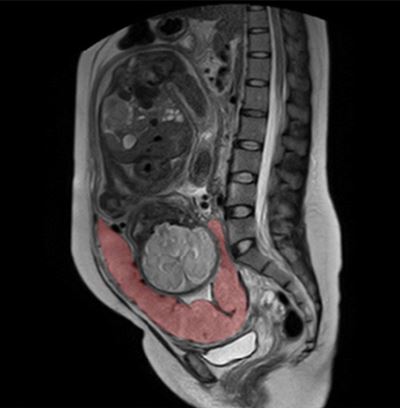

Detection of invasive placenta is important as it necessitates special attention and treatment. A combination of US (anterior placenta) and MRI (posterior placenta) allows for reliable detection and staging.

Article: Identification of suspicious invasive placentation based on clinical MRI data using textural features and automated machine learning